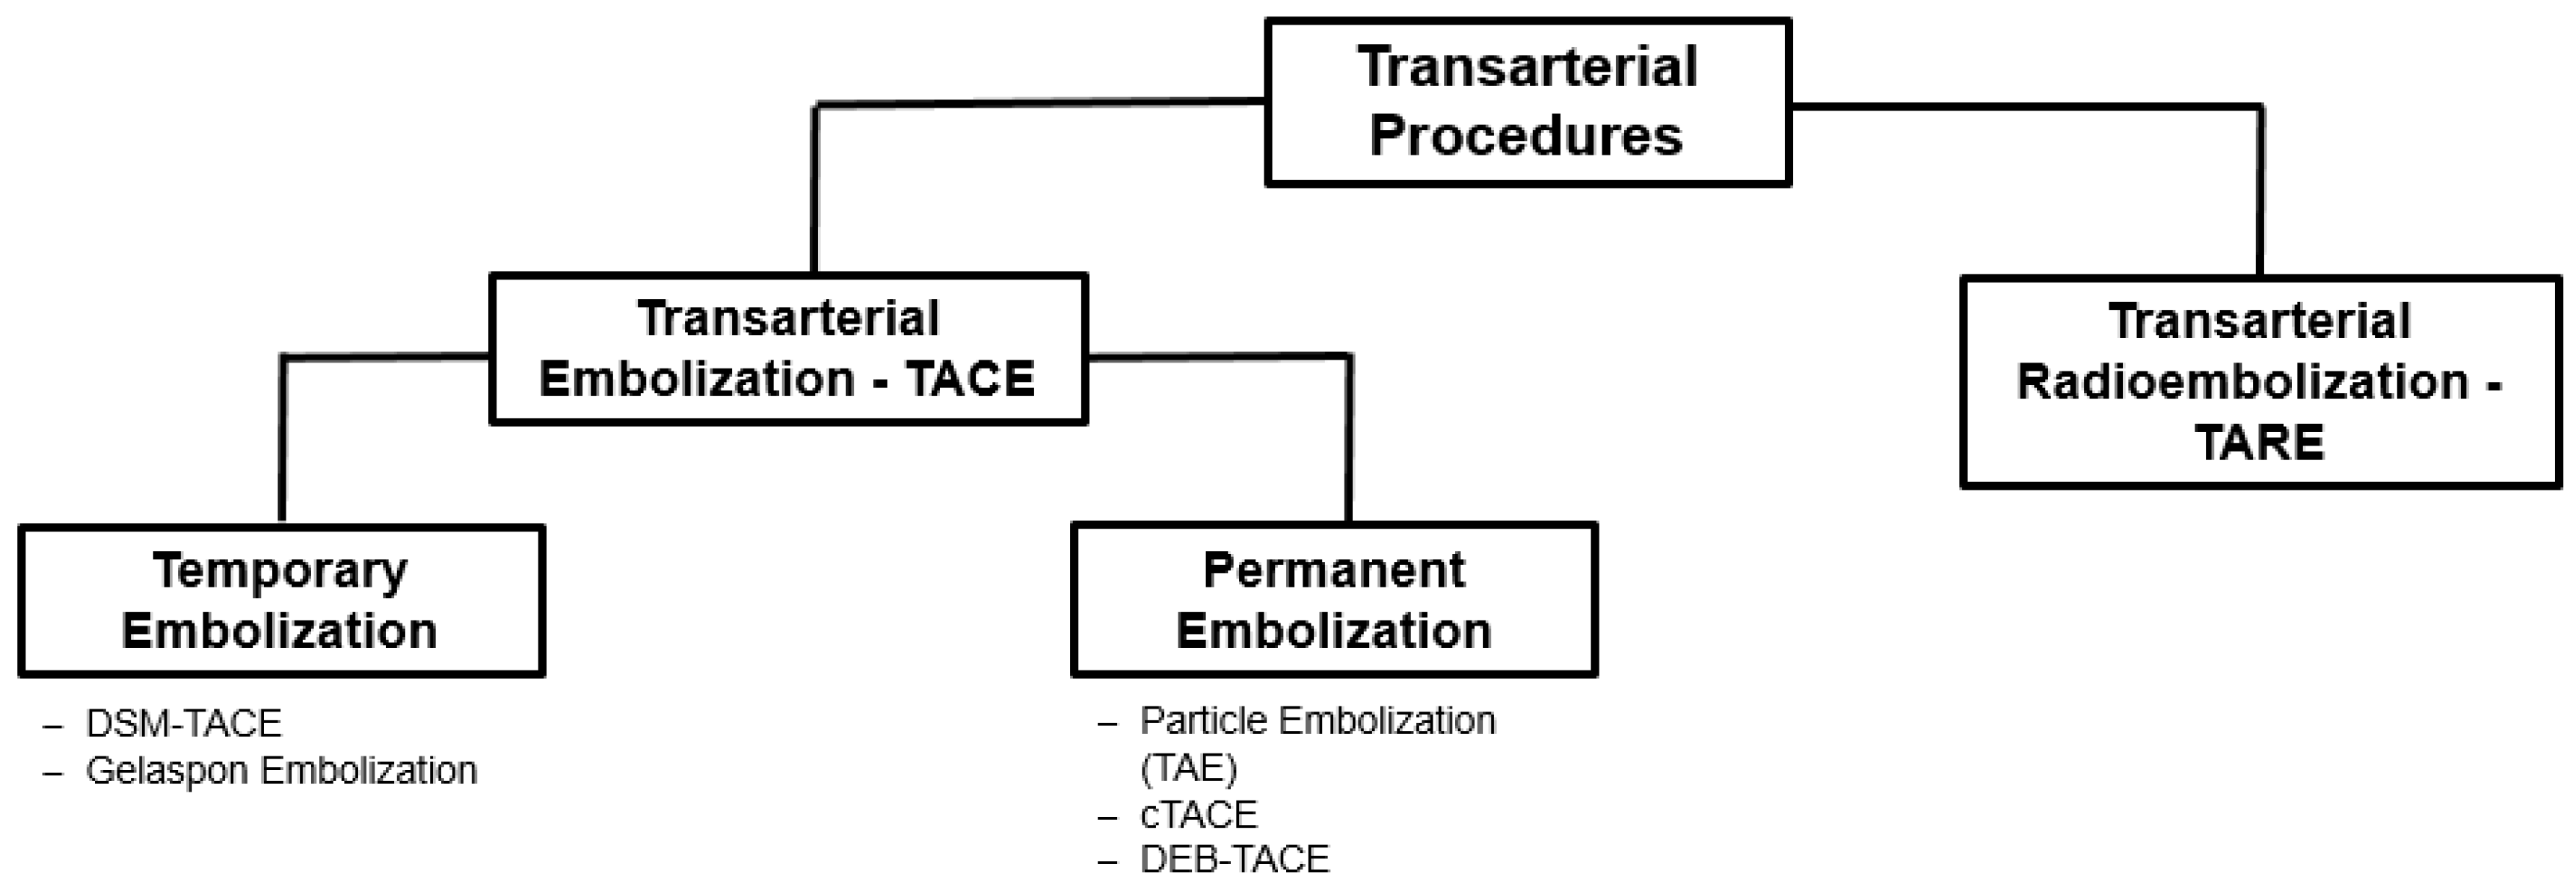

3. Transarterial Procedures

3.1. Transarterial Chemoembolization (TACE)

3.2. Transarterial Radioembolization (TARE)